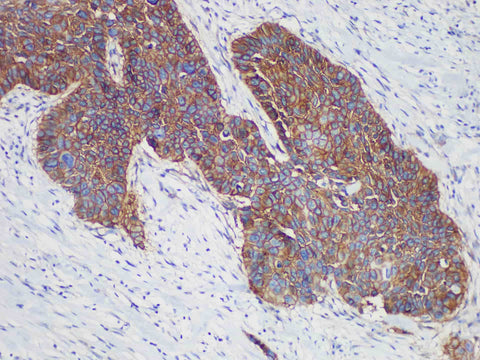

Applications IHC-P

Tissue Specificity esophageal squamous cell carcinoma

Epidermal growth factor receptor (EGFR) is a receptor-type tyrosine kinase, which is overexpressed or mutated in many tumors. It controls tumor growth through signal transduction, and is closely related to angiogenesis, tumor invasion and metastasis. Studies have shown that EGFR is overexpressed in breast (25%), brain, bladder, lung, stomach, esophagus, cervix, ovary, and endometrial tumors. It is currently used as a reference for targeted therapy of non-small cell lung cancer.